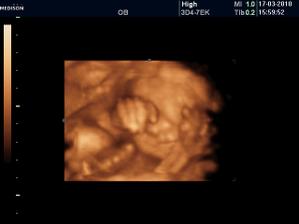

Vyrobene z velkej lasky